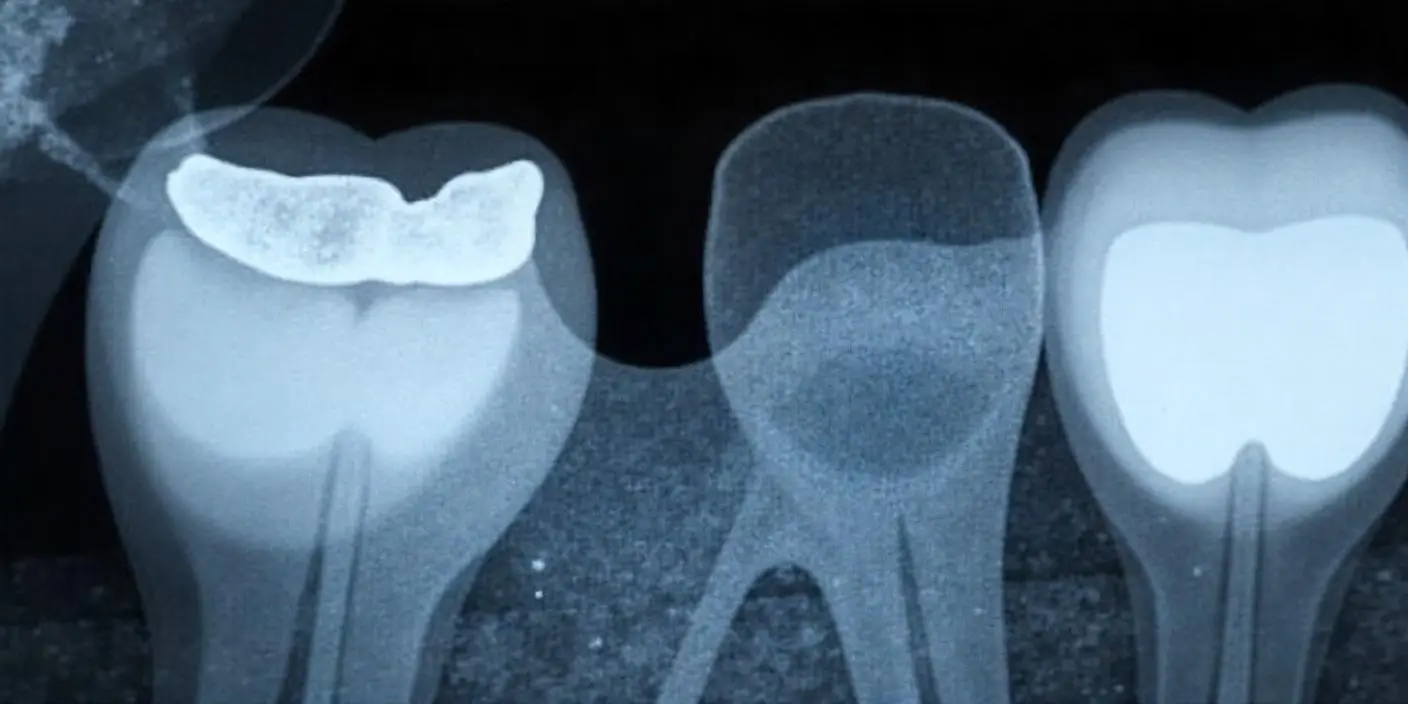

임플란트 주위염이란? 증상과 위험성

임플란트 주위염은 말 그대로

임플란트를 둘러싼 잇몸과 뼈에 염증이 생기는 질환입니다.

자연치아의 잇몸병과 비슷하지만, 골 손실이 빠르게 진행되기 때문에

조기에 발견하고 치료하지 않으면 임플란트를 제거해야 하는 상황까지 올 수 있습니다.

✅ 임플란트 주위염의 주요 증상

- 잇몸이 붓고 붉어지며, 누르면 피가 남

- 임플란트 주변에서 고름이나 분비물이 나옴

- 칫솔질할 때 출혈이 자주 발생

- 입 냄새가 심해짐

- 씹을 때 통증 또는 느슨해진 느낌

- 시간이 지나면서 임플란트가 흔들리는 경우도 있음

✅ 왜 위험한가요?

- 염증이 턱뼈까지 퍼지면 임플란트를 지지하는 뼈가 녹아내리게 됩니다.

- 이렇게 되면 보철물을 빼고, 뼈 이식 등 추가적인 수술이 필요해질 수 있습니다.

- 특히 당뇨, 흡연, 구강 위생 불량이 있는 경우 더 쉽게 발생합니다.

📌 임플란트 주위염은 조용히 진행되다가 갑자기 큰 손상으로 이어질 수 있으므로,

정기적인 검진과 올바른 구강 관리로 예방하는 것이 가장 좋습니다.